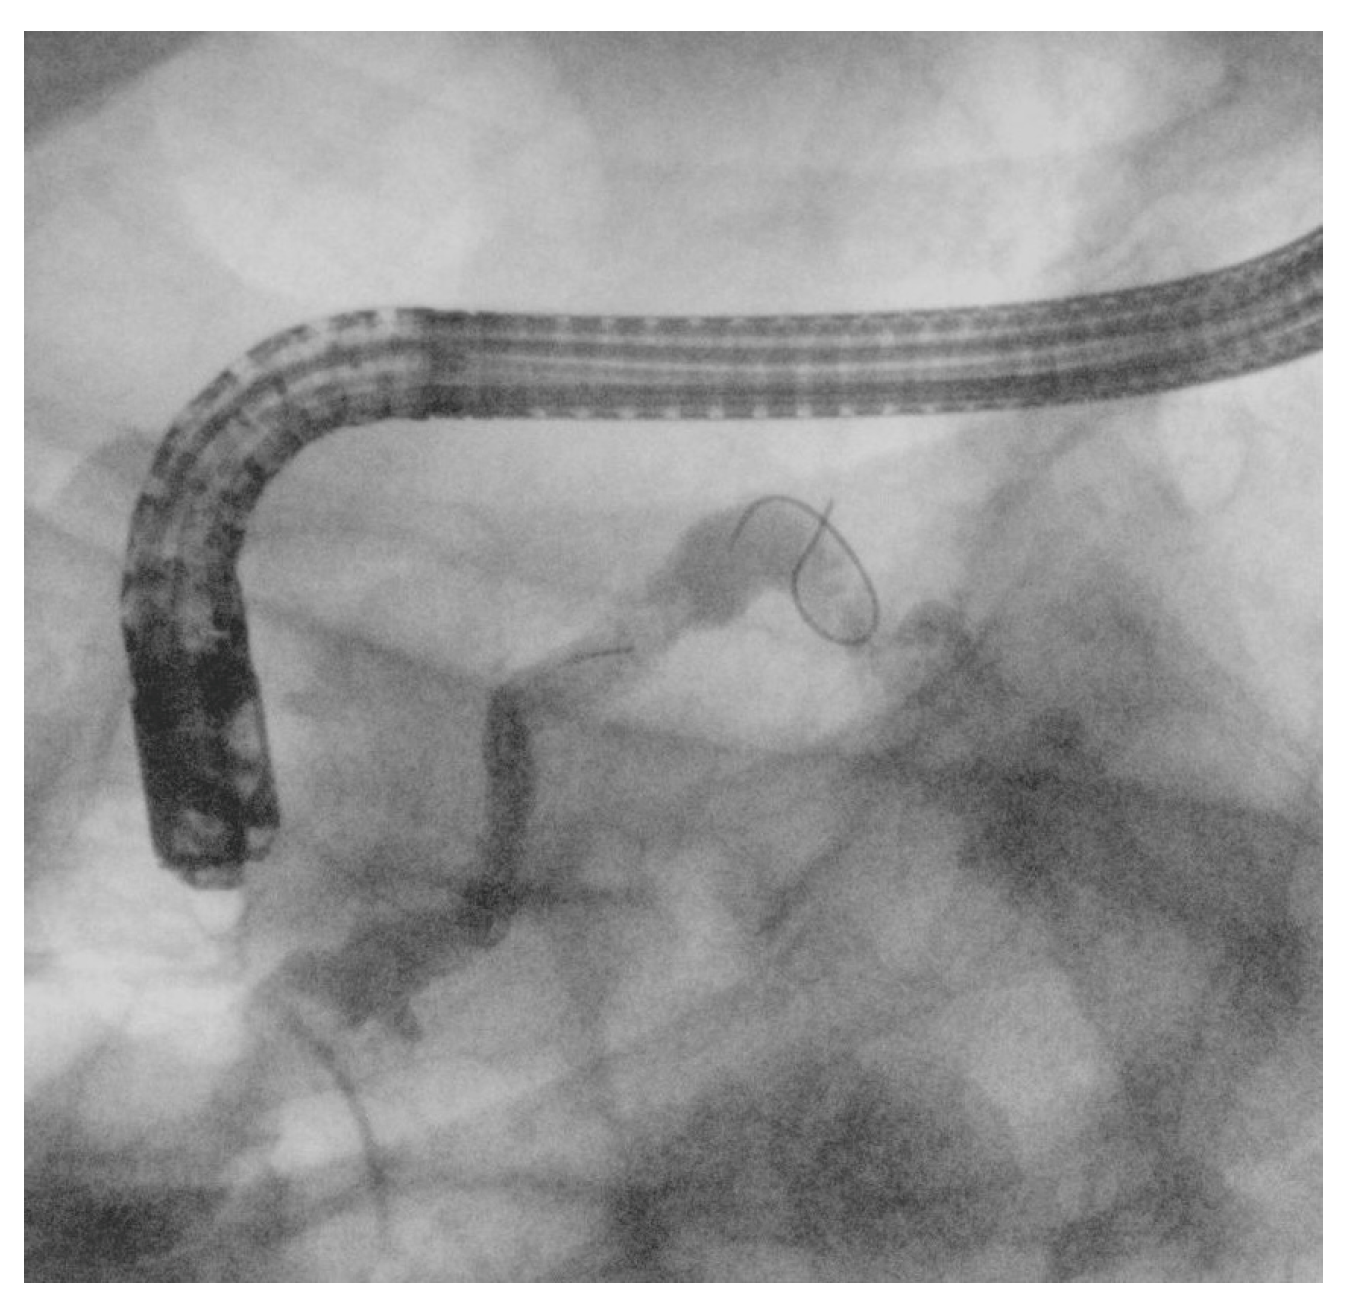

4.2. EUS–Pancreatic Drainage (EUS-PD)

Two main approaches for EUS-PD exist: EUS-Rv, where a small-caliber wire is advanced in an antegrade manner into the duodenum for ERCP stenting (Figure 8), and EUS-PD transmural drainage, involving serial dilation and stent placement from the stomach or the duodenum (pancreaticogastrostomy/pancreaticoduodenostomy) [50]. Successful EUS-PD relies on precise pancreatic duct puncture and effective guidewire manipulation, given the small duct size, side branches, and potential strictures. A 19-gauge needle with a sharp tip and a 0.025-inch flexible-tip guidewire is generally recommended [51]. In cases with a small pancreatic duct, a 22-gauge needle combined with a smaller (0.018-or 0.021-inch) guidewire may be used, though these thinner guidewires can be challenging to manipulate even after successful duct puncture [52]. The advantage of the 22-gauge needle lies in its ability to puncture even a fibrotic pancreas or a stiff, narrow MPD; in their single-center retrospective study, Matsunami et al. reported high technical success in EUS-PD using a 22-gauge needle despite targeting a small MPD (median diameter 3.5 mm, range 1–14 mm) [53]. However, due to the limited fluoroscopic visibility and insufficient shaft stiffness for therapeutic device support that 0.018- and 0.021-inch guidewires typically offer, when initial access is achieved with a smaller guidewire, a subsequent exchange to a larger-caliber (0.025- or 0.035-inch), stiffer wire is often necessary to ensure procedural success [54]. Studies such as those by Inoue et al. [55] and Sasaki et al. [56] have noted the value of an ultra-tapered or hybrid wire with a stiff body to facilitate pushability and a soft tip to minimize ductal trauma. For patients with surgically altered anatomy, such as those who have undergone gastrectomy, selecting an appropriate puncture site can be difficult due to the reduced stomach volume. In such cases, transjejunal EUS-PD is an ideal approach, as the jejunum and pancreatic duct are closely anastomosed. A stiff guidewire, typically used for endoscopic long intestinal tube insertion, helps optimize this technique. After straightening the twisted afferent jejunal loop using an enteroscope, the guidewire is placed to maintain the loop’s shape. Additionally, by deploying the guidewire into the working channel of a forward-viewing echoendoscope (ropeway method), smooth scope insertion is achieved, facilitating the transjejunal EUS-PD procedure [57].

Figure 8. Radiological image of the EUS-PD rendezvous technique. (a) After placing a stent across pancreaticogastrostomy, the guidewire is advanced in an antegrade manner into the pancreatic duct under EUS guidance, followed by standard ERCP and transpapillary stent placement over the wire for pancreatic duct drainage. (b) The end of the procedure with the two stents (highlighted by the red arrows) in the main pancreatic duct.